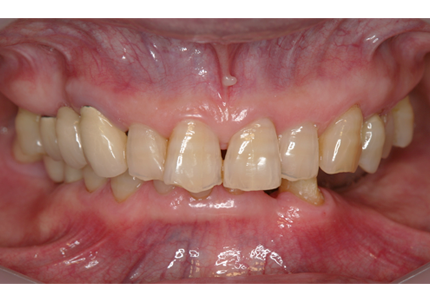

1.初診時(2006年5月)

2.上顎補綴物除去

1.初診時口腔内(2007年6月30日)